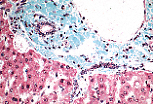

该视野显示人肝中的伊东细胞(Ito细胞); 该细胞位于狄氏间隙内,可通过弯曲的细胞核和脂质包涵体识别。

伊东细胞的功能之一是储存维生素A。